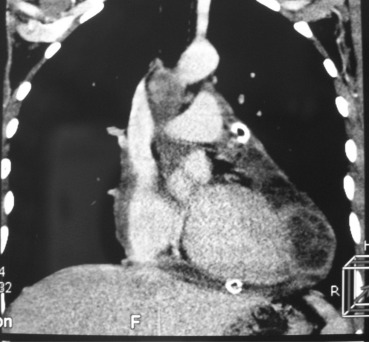

An urgent pericardiocentesis was performed and 1.1 L of serofibrinous fluid was drained. Pericardial fluid cytology and cultures for bacteria, tuberculin skin test, and blood cultures were negative. Serologic tests for hydatidosis were negative. Clinical improvement was prompt and repeated echocardiography confirmed regression of pericardial effusion and persistent cystic mass inside the pericardial cavity containing mixed echogenic floating circles characteristic of a hydatid cyst. A computed tomography (CT) scan of the head, chest, and abdomen also detected a multilocular well-bordered cystic mass with internal trabeculae, widely attached to pericardium, extending into the pericardial sac and compressing the left ventricle without involvement of the heart muscle. There were no cysts in the brain, lungs, liver, or elsewhere (Fig. 2).

Computed tomography scan revealing multilocular well-bordered cystic mass with ...

Figure 2.

Computed tomography scan revealing multilocular well-bordered cystic mass with internal trabeculae, widely attached to the pericardium, extending into the pericardial sac and compressing the left ventricle and a drain placed into the pericardial sac.